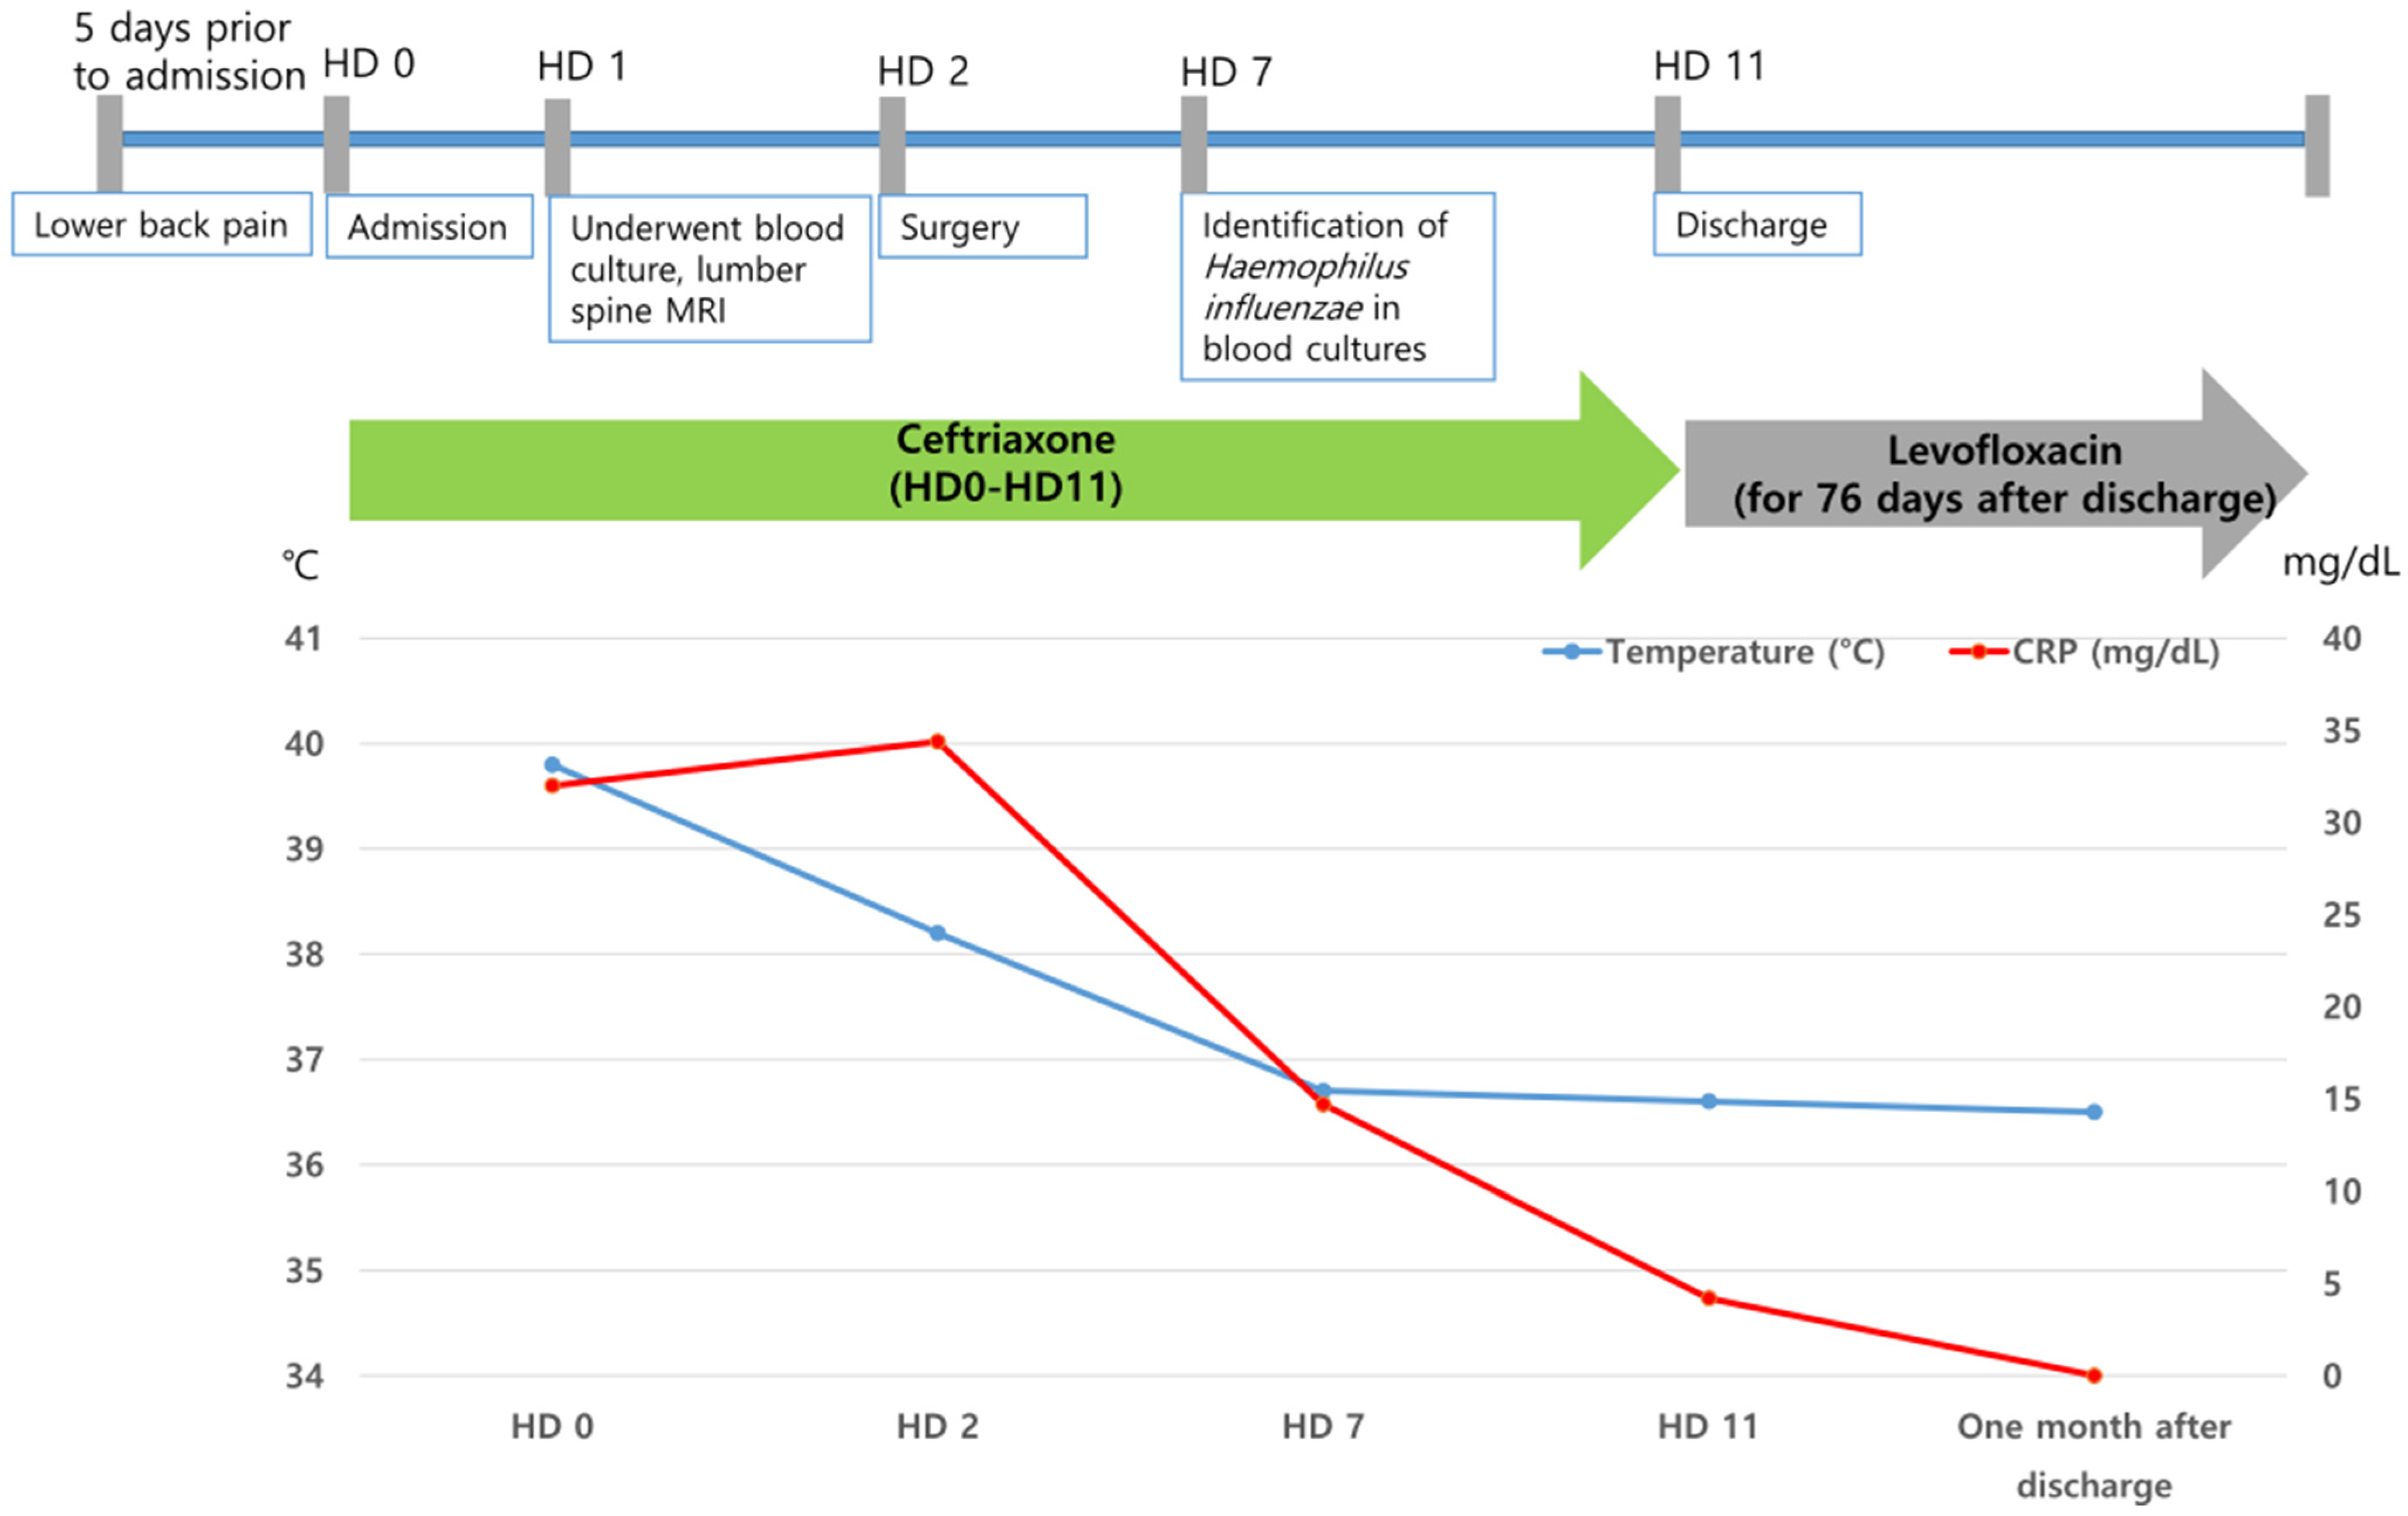

2. Case Presentation

| 3 | F/53 | Lumbar spine disc herniation | Right lower back pain with radiating pain in the right thigh Fever | No | L4-5 | None | None | No | Yes (HD 2) | Ceftriaxone (11 days) → levofloxacin (76 days) | Survived | No | This case |